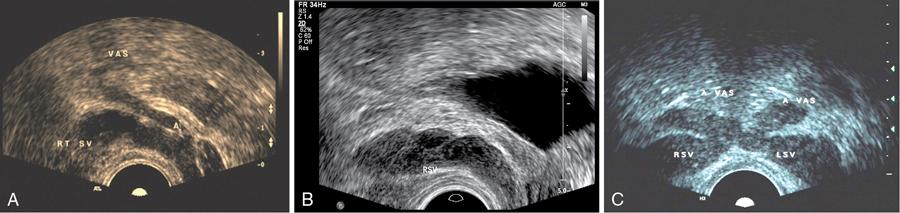

Anidudha Kulkarni Seminal vesicles (SVs) are an integral part of male genitourinary system. SVs are paired accessory gland which plays a major role in male fertility. They produce an alkaline fluid contributing 50%–80% of the ejaculate volume. Male genital organs collectively work to produce semen, consisting of mature spermatozoa. There are no specific signs and symptoms for pathologies in SVs. The common complaints include pain, recurrent UTI and dysuria. Commonly, an abnormality is identifies while investigating for an unrelated pathology such as infertility or a prostatic nodule. SVs are paired organs, measuring 5–7 cm in length, which are rounded superiorly and taper inferiorly. SVs are located posterior to the bladder and inferolateral to the vas deferens. This bilateral positioning of the SVs creates a ‘V’-shaped configuration. SVs are positioned superior to prostate. They lie at the inferior aspect of the rectovesical pouch. SV ducts merge with ampulla of vas deferens and form the ejaculatory duct which opens into the prostatic urethra at the level of verumontanum. SVs contain highly granular cells that produce straw coloured alkaline fluid containing fructose, proteins and vitamin C under the influence of testosterone. The fructose provides the required energy for the motility of spermatozoa. This fluid makes up two-thirds of the total ejaculate volume. Rest of which comes from the prostate gland, vas deferens and lesser amounts from bulbourethral and Cowper’s glands. SVs appear as fluid-filled structures, with a thin septations on contrast-enhanced CT. This modality remains helpful in recognizing many SV abnormalities. On MRI they show low signal intensity on T1-weighted and high signal intensity on T2-weighted images and appear as elongated fluid-filled structures with thin septae. SVs appear as symmetric organs which lie cephalad to the prostate and posterior to the bladder They have a typical ‘bow-tie’ appearance in transverse scans and a club or tennis-racket shape in longitudinal scan. They show homogenously fine echoes, however they are less echogenic than prostate. SV volume is positively affected by circulating testosterone and prolactin, and increases during a prolonged sexual abstinence. Volume of SVs tends to shrink after the fifth decade. SV agenesis is a rare congenital anomaly with an incidence of 0.08%, where there is a complete or partial absence of one or both SVs. This anomaly results in infertility secondary to azoospermia. Patients are generally asymptomatic. Only symptom is infertility and thin low volume ejaculate. TRUS remains the modality of choice to diagnose patients with SV agenesis. There is no treatment available for the SV agenesis. The ureteric bud develops from the mesonephric duct during the 5th week of intrauterine life. In the 7th week, the testes develop and differentiate the male genital system. SVs develop as a bulbous swelling of distal portion of mesonephric duct during the 12th week of gestation. SVs are retrovesicle to the urogenital sinus. SV agenesis is often associated with abnormal development of other mesonephric/metanephric derivatives, such as the VD, ureter and kidney. Unilateral SV agenesis is due to insult occurring before the 7th week of gestation, when the ureteric bud arises from mesonephric duct. Bilateral SV agenesis is related to CFTR gene mutations (64%–73% of cases). A decreased SV volume is defined as hypoplasia, and mainly refers to congenitally small SV, although an acquired form may be associated with testosterone deficiency or postinfective scarring. The normal SV measures >25 mm in length. They are considered to be hypoplastic when >16 mm but <25 mm and atrophic when <16 mm Another parameter which can be considered for hypoplasia is the maximum anteroposterior diameter being smaller than 50% of normal or <5 mm. Hypoplasia of the SVs may be unilateral or bilateral. This condition usually is associated with other genitourinary anomalies such as absence of the ipsilateral vas deferens and ejaculatory ducts.